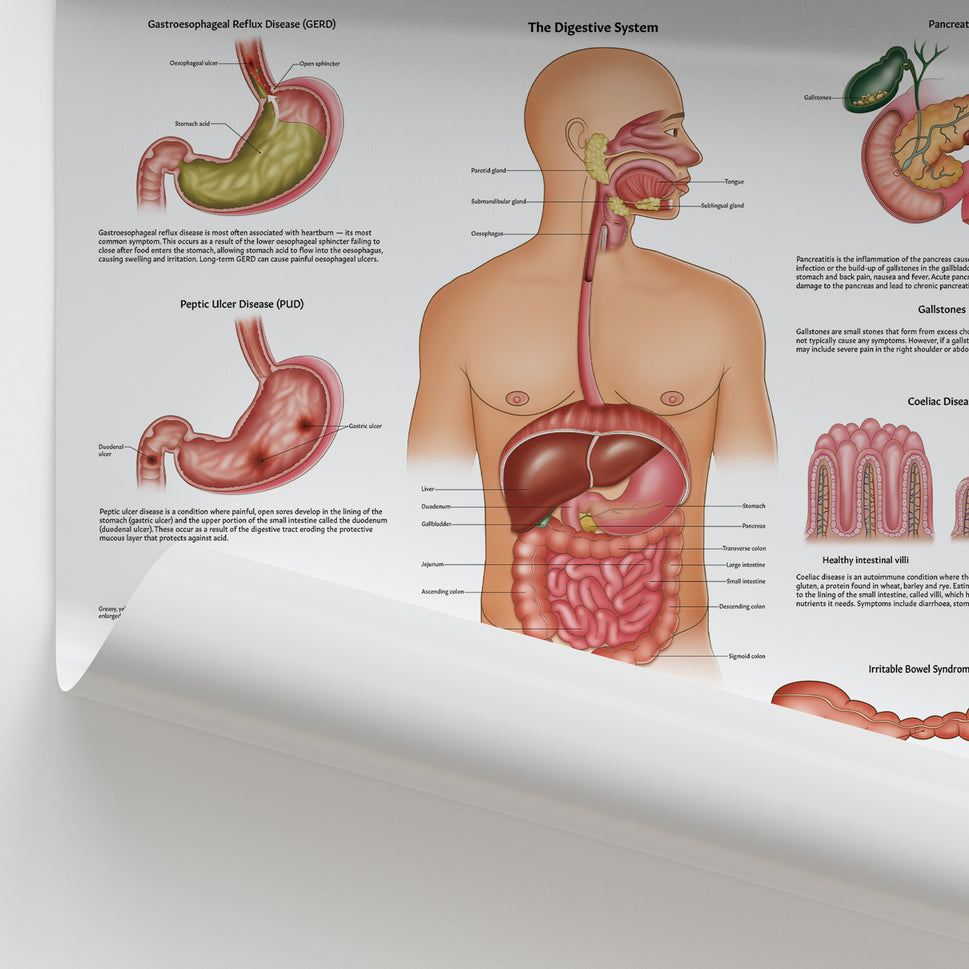

Enhance medical education with our collection of digestive system anatomical models including the stomach, liver, gallbladder, pancreas & colon models. Discover the anatomy of healthy organs as well as common gastrointestinal diseases such as stomach ulcers, gallstones and liver cirrhosis. Our digestive system anatomy posters are ideal for study and patient education.

At AnatomyStuff we stock a diverse range of digestive system anatomical models to suit your training needs. From budget models and affordable medical education posters to highly advanced 3D printed bowel models, you can transform medical training and patient education. As well as our own exclusive collection, we are proud resellers of 3B Scientific, Anatomy Lab, Denoyer-Geppert Science Company, ESP Models, Erler Zimmer and GPI Anatomicals. Explore our exclusive collection of digestive system anatomy charts, posters, fine art prints and digital anatomy study guides. Discover the anatomy of key organs like the liver, stomach, pancreas and bowel as well as the pathophysiology of common conditions like peptic ulcer disease, coeliac disease, IBD and much more. We have anatomy posters suitable for school children all the way up to medical degree level. From a liver anatomy poster to a digital study guide all about common GI disorders, find exactly what you need right here to enhance medical training and patient education.